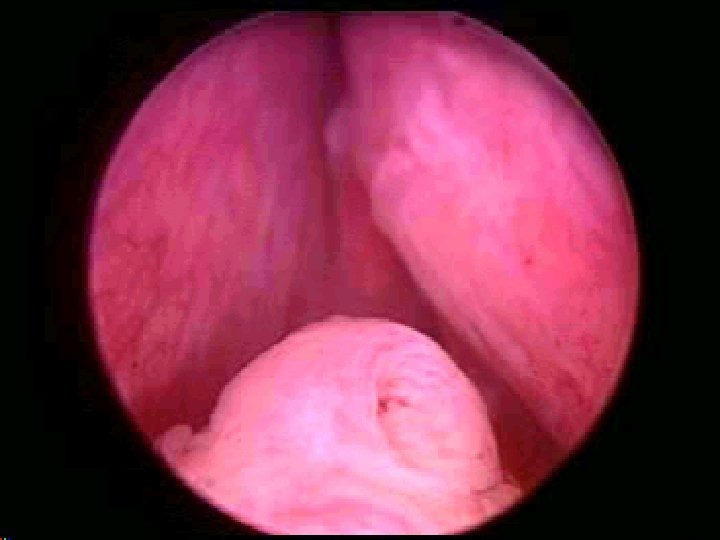

Indication Refractory urinary retention Recurrent urinary tract infections

Indication • Refractory urinary retention • Recurrent urinary tract infections due to prostatic hypertrophy • Recurrent gross hematuria • Renal insufficiency secondary to bladder outlet obstruction • Bladder calculi • Permanently damaged or weakened bladders • Large bladder diverticula that do not empty well secondary to an enlarged prostate